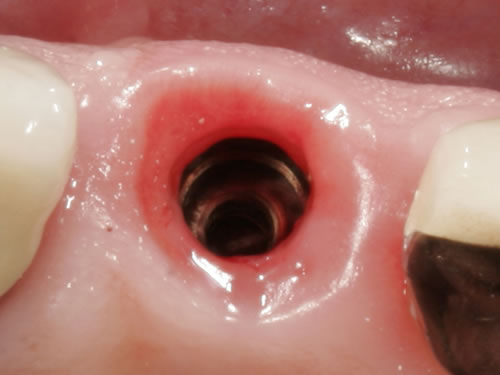

Implantate können einteilig oder mehrteilig sein. Gängiger sind mehrteilige, zusammengesetzte Implantate. Sie bestehen aus drei Teilen: dem Körper, der im Knochen verankert wird, dem Kopfteil, auf dem die künstliche Zahnkrone befestigt wird, und dem Halsteil, der genau zwischen diesen beiden Teilen liegt, im Mund also im Bereich der Schleimhaut. Nach einer Einheilungszeit des Implantatkörpers im Kieferknochen wird die Zahnkrone für jeden Menschen und für jede Kieferregion in spezieller Form und Farbe angefertigt und z.B. in einer Steck- Schraubverbindung des Implantates fixiert (Abb. 2.2).

Abb. 2.2: Innengeometrie eines eingesetzten Implantates.

Die meisten Implantate heilen zunächst über einige Monate unbelastet ein und werden erst dann mit einer künstlichen Zahnkrone versorgt. Die Verbindung dieser Krone mit dem Implantat erfolgt in der Regel über eine Steck-Schraubverbindung, das sich im Inneren des Implantates befindet (Abb. 2.2). Die Aufbauten werden in diesem Gewinde verschraubt oder zementiert.